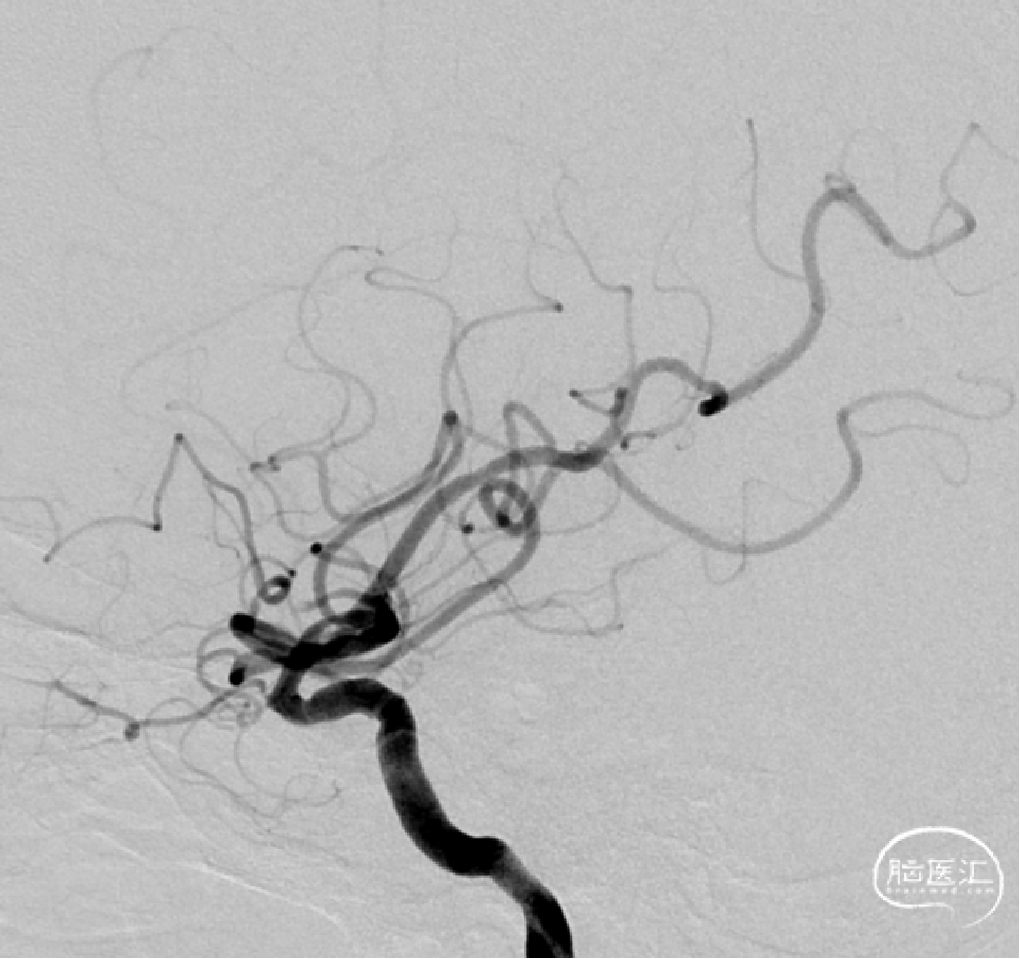

颅内球囊 2.25*15mm扩张,扩张至10个atm。

狭窄改善。

植入Atlas支架,动脉瘤不显示,狭窄改善。

术后正侧位。

颅内动脉瘤伴载瘤动脉狭窄,予填塞动脉瘤同时予球囊扩张狭窄血管并予支架植入,一次手术同时解决两个病变,减少患者手术次数及手术费用。